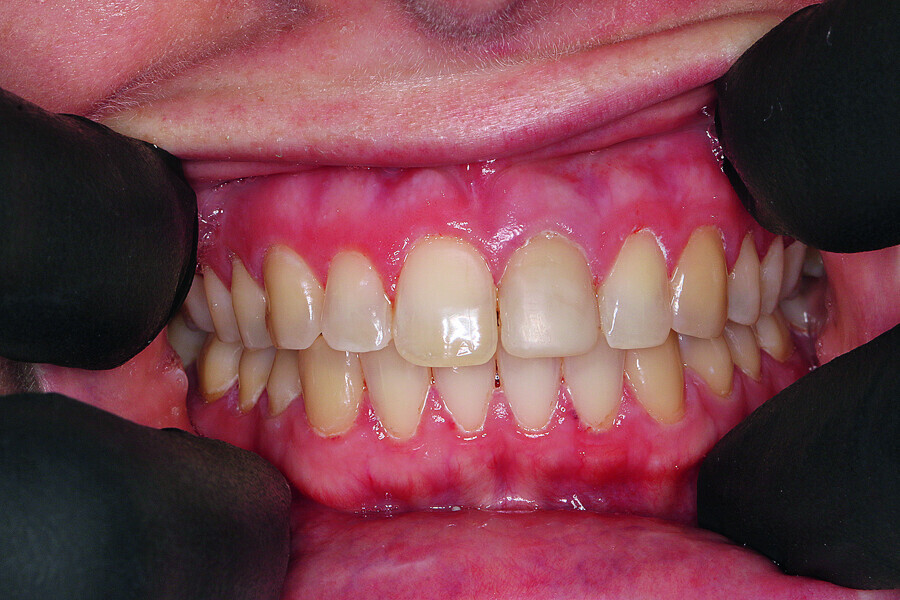

Fig. 4: Tooth #21 was deleted in CEREC to simulate the initial post-op situation.